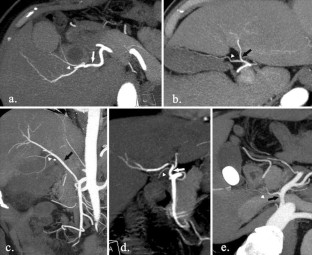

Assessment and classification of cystic arteries with 64-detector row computed tomography before laparoscopic cholecystectomy

Major complications of laparoscopic cholecystectomy are bleeding and bile duct injury, and it is necessary to clearly identify structures endoscopically to keep bleeding and injury from occurring. The aim of this study was to depict the anatomical variation between cystic arteries among patients using 64-detector row spiral computed tomography (CT) prior to laparoscopic cholecystectomy.

A total of 78 patients (31 men, 47 women) who underwent cholecystectomy were examined preoperatively using 64-detector row spiral CT between April 2012 and June 2013. The origin and number of cystic arteries and their relationship with the Calot triangle was evaluated by two independent observers. CT images were compared with laparoscopic cholecystectomy results.

The cystic arteries were delineated by CT in 73 of the 78 patients. The relationship between the cystic arteries and the Calot triangle was identified in 71 of the 78 patients. One cystic artery was found in 53 (73 %) of the 73 patients, while two cystic arteries were found in 20 (27 %) of the patients. A total of 55 (60 %) of the 91 cystic arteries passed through the Calot triangle. The remaining 36 cystic arteries (40 %) passed anterior, posterior, or inferior to the cystic duct. The relationship between the cystic arteries and the Calot triangle detected by CT was in agreement with the surgical records for all patients.

The configuration of the cystic arteries and their relationship with the Calot triangle can be identified using 64-detector row CT before laparoscopic cholecystectomy.

Fig. 4